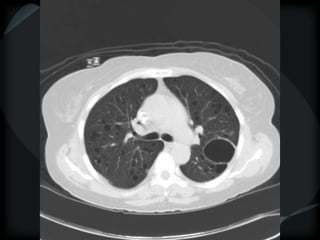

RETICULAR PATTERN - UIP

 peripheral reticular lines / inter and intralobular septae

 honeycomb

 Traction bronchiectasis

 None or minimal ground glass

 Gradient increasing from apex to base

 Skip areas

 Diagnostic accuracy high

 Idiopathic

 Familial

 CVD - RA

 Drugs – NFT, Busulphan

 Asbestosis = basilar – bands – pleural calcification

 Chronic HP = upper and midzones

 Hermansky-Pudlak syndrome

Acute exacerbation of UIP

● above + ground glass

● Peripheral – better prognosis – Fibroblastic Foci+++

● Diffuse – worse prognosis – DAD

AMJRCCM.198:372;2008